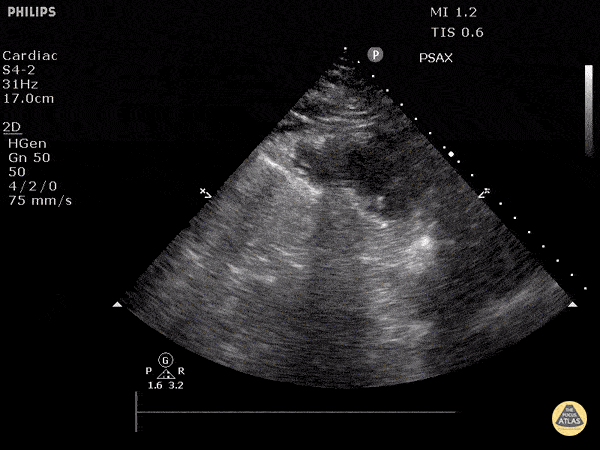

Parasternal kısa aks

Sağ ventrikül fonksiyonunun değerlendirilmesi

Sağ ventrikül, önceki bölümde anlatılan temel kardiyak pencereler kullanılarak değerlendirilebilir. Normalde sağ ventrikül düşük basınçlı bir odacıktır ve sol ventriküle kıyasla daha küçük görünür.

Sağ ventrikül disfonksiyonunda özellikle şu bulgulara bakılır:

Sağ ventrikül dilatasyonu

Septal bombeleşme (septal bowing)

Kısa aks görüntüsünde, pulmoner arter basıncının artmasına bağlı olarak sağ ventrikül genişledikçe interventriküler septum sol kalbe doğru bombeleşir. Bu durum sol ventrikülde D-şekilli görünüm (D-sign) oluşturur.

Apikal dört boşluk görüntüsünde sağ ventrikül normalde sol ventrikülün yaklaşık üçte ikisi büyüklüğünde olmalıdır. Eğer iki ventrikül aynı boyutta görünüyorsa bu durum anormal kabul edilir ve dilatasyon düşündürür.